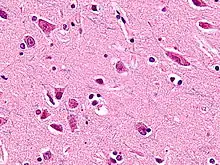

Micrograph showing a von Economo neuron of the cingulate. HE-LFB stain.